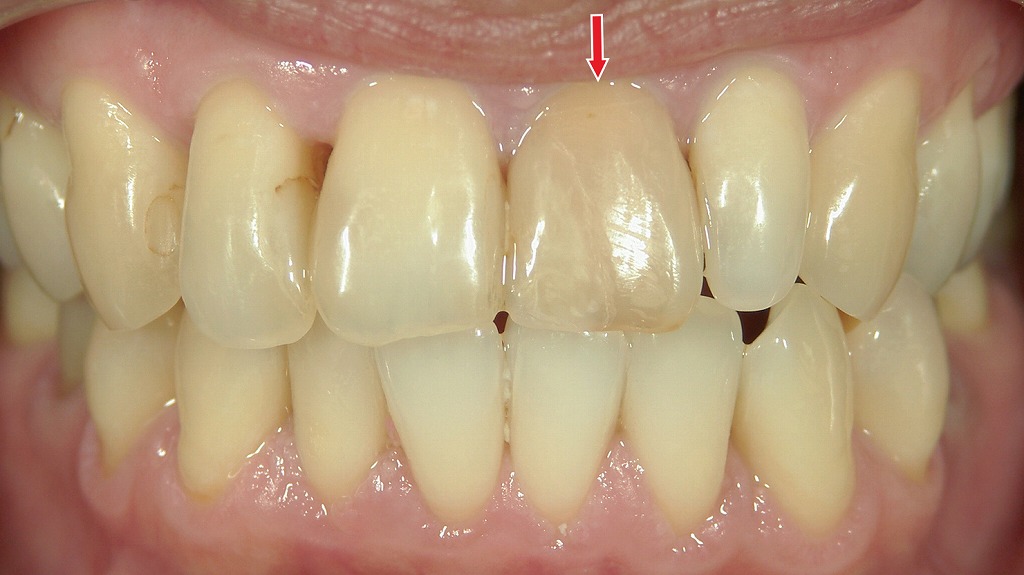

◆ホワイトニング術前

術前:全体的に黄ばみがある状態。失活歯(矢印)は内部の変色が進んでおり、周囲の天然歯と同様に黄ばみが強く出ています。

◆ホワイトニング術後

術後:通常のホワイトニングで天然歯は明るく白くなった一方、失活歯だけは色が変わらず暗いまま。神経のない歯は内部からの漂白(ウォーキングブリーチ)など特別な処置が必要です。